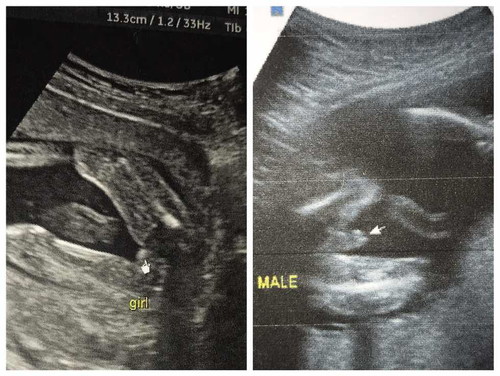

เพศ

จากที่ถามไปเมื่อคืนนี้ดันไปเอารูปอัลตราซาวน์ลูกชายคนเเรกลง นี่คะซาวน์19week คุณหมอบอก ผญ. เเบบนี้จะ ผญ.100%ไหมนะ

แม่ว่า... 👧 ชัดมากค่ะ 😂